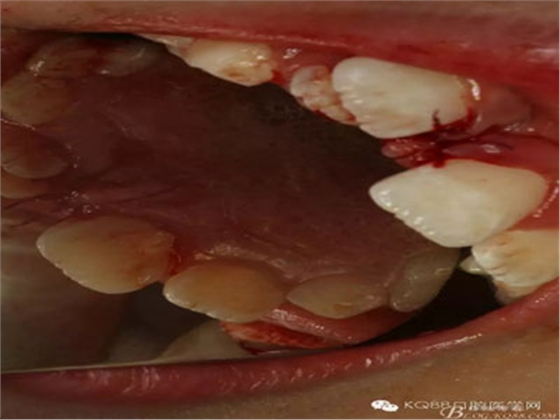

圖1.術(shù)前的患者口內(nèi)照片:11與12完全唇腭向重疊,11與21之間有3mm間隙